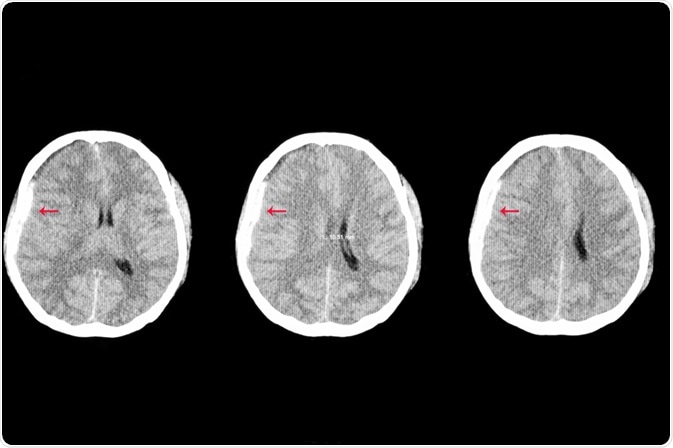

Certain diagnostic methods, like MRI brain scans, can provide your doctor with the best possible information about the severity of your TBI and determine essential prognostic information. This can help ensure you get the treatment you need.